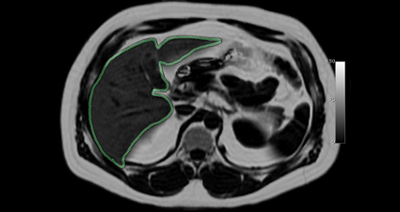

Magnetic Resonance Imaging (MRI) is one of the most diverse imaging modalities in medicine and offers the ability to take images of specific biological tissues. The two most common tissues within the human body are water and fat. Recently it has been discovered that when some organs (specifically the liver) are un healthy, they will contain high levels of fat. In order to diagnose diseases, it is critical to determine an accurate estimate of the amount of fat within the liver (outlined in green).

The current gold standard is to use a liver-biopsy, however this is an invasive method that only samples a small portion of the liver and can lead to misdiagnosis. The objective of our research is to use MRI to quantify the amount of fat within the entire liver. MRI techniques have been developed in the past that are able to form “purely-fat” and “purely-water”(normal liver tissue) images, however this makes the MRI scan longer.